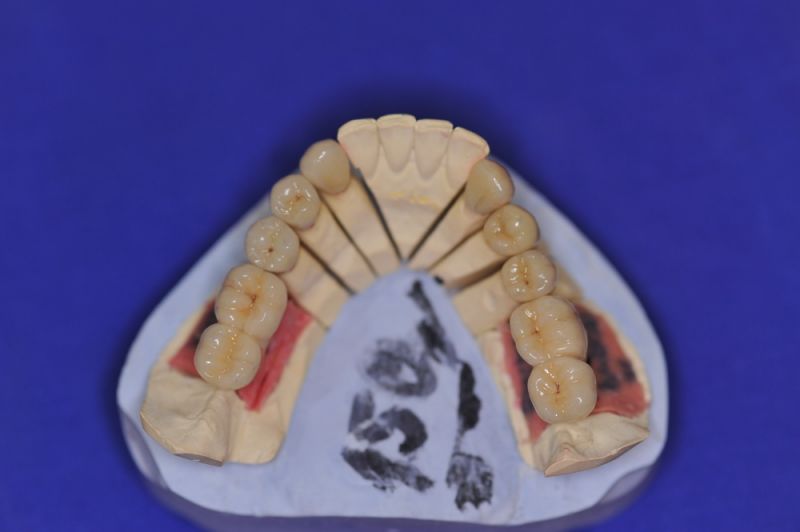

Mit dem heutigen Tag geht eine der technisch schwierigsten und anspruchsvollsten Arbeiten zu Ende, die im CMD-CENTRUM-KIEL jemals erstellt worden ist. Dabei sind es nur 10 Kronen, die benötigt werden, um die starken Kopf- und Gesichtsschmerzen der Patienten zu beseitigen.

Die Lösung einer Vielzahl technischer Probleme, die vorrangig verursacht waren durch:

1. Notwendigkeit einer implantatgestützten Kronenversorgung mit der Vorgeschichte, dass die Patientin eine Vielzahl von Behandlern aufgesucht hatte, die eine Implantation im Unterkiefer als nicht durchführbar einschätzten.

3. Sehr dünne Implantate, die von ursprünglich zwei je Kieferhälfte auf letztendlich drei je Kieferhälfte umgeplant werden mussten.

4. Notwendigkeit die Mundhygienefähigkeit der Arbeit auch unter sehr beengten Verhältnissen zu schaffen, um der Arbeit eine günstige Prognose mitzugeben.